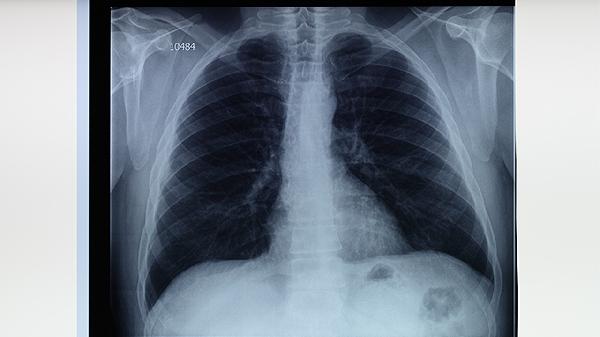

肺结核是一种传染性疾病,患者需注意隔离,避免传染他人。治疗过程中可能出现各种副作用,需及时与医生沟通,调整治疗方案。定期复查胸片和痰检,监测病情变化,是确保治疗效果的重要措施。